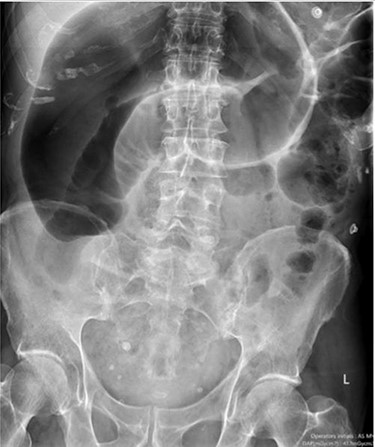

Blood tests on admission were unremarkable. Each admission, the patient’s plain abdominal films showed dilated large bowel loops consistent with sigmoid volvulus (Fig. 1). A subsequent computed tomography (CT) of the abdomen and pelvis with intravenous contrast revealed dilated large bowel and was reported as sigmoid volvulus with no evidence of perforation (Fig. 2). Caecal volvulus was not appreciated on this scan.

Case one: plain abdominal film showing dilated large bowel and the ‘coffee bean’ sign associated with sigmoid volvulus.